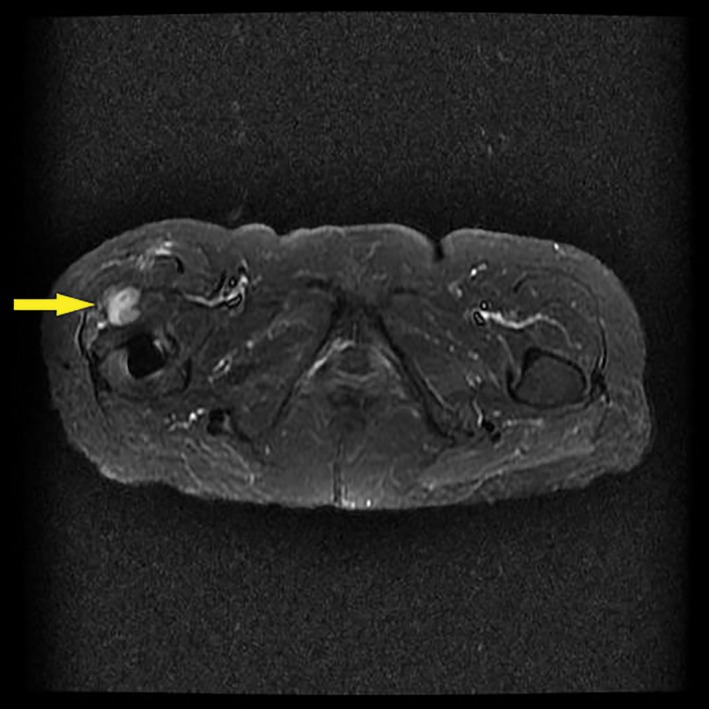

In the MoM group, 11 patients developed a peri‐prosthesis pseudotumor, including 2 C3 level cases, 6 C2 level cases, and 3 C1 level cases. In the MoP group, 4 patients developed pseudotumors according to the same diagnostic criteria, including 1 C3 level case, 2 C2 level cases, and 1 C1 level case. The occurrence rate of pseudotumors in the MoM and MoP groups was, respectively, 40.74% ± 9.45% and 14.28% ± 6.61% (u = 2.2032, P < 0.05; Figs 4 and 5).

Figure 4.

A metal artifact reduction sequence (MARS)‐MRI scan showing a pseudotumor in 1 patient 74 months after the primary total hip arthroplasty with a metal‐on‐metal (MoM) prosthesis.